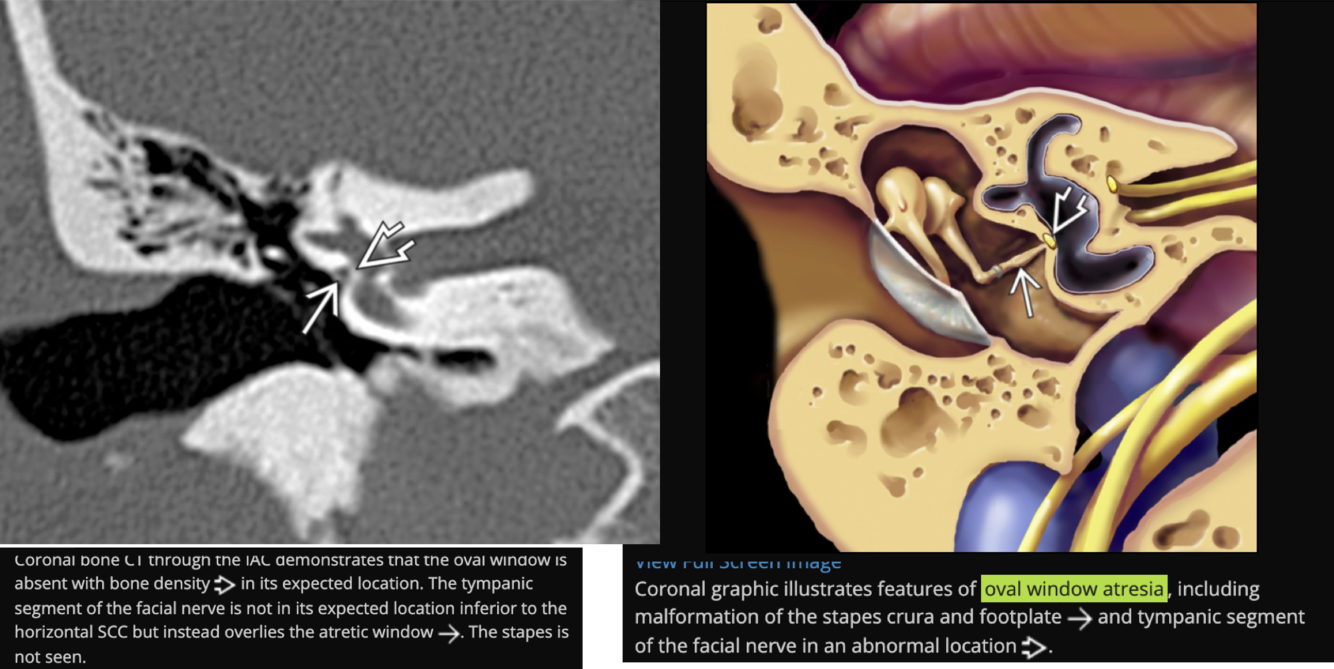

**Tympanic segment of the facial nerve will always be aberrant in the location of the oval window instead of inferior to the lateral semi-circular canal

Prolapsing facial nerve (protruding intratemporal facial nerve)

Tubular soft tissue prolapsing into oval window niche from undersurface of LSC. Caused by dehiscence of bony covering of the facial nerve.

No enhancement! If enhances then it is a Schwannoma.

May project into oval indow.